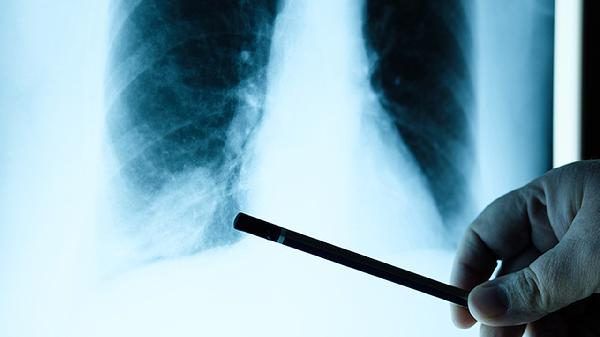

从明年开始,超过65岁以上的癌症患者,一定要做好这8个准备

你是否有留意到,每年体检报告上那些微小变化?当银发悄然爬上鬓角,身体这台精密仪器也开始需要更多呵护。对于年过六十五的朋友来说,面对健康挑战就像准备一场未知的旅行,提前打包好行囊才能从容出发。